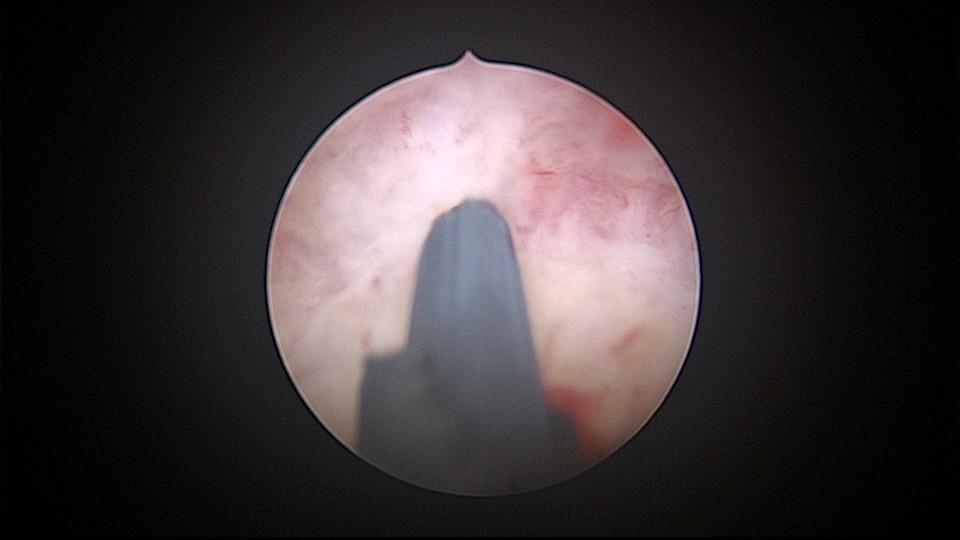

患者32岁,G6P2,顺产2次。2025年3月,停经56天,计划外妊娠,要求终止妊娠并放置节育环,考虑终止妊娠后宫腔大,担心环移位或脱落,要求固定节育环。γ环没有尾丝,用4号丝线连接环及不锈钢挂钩,将挂钩插入宫底肌层固定,异物钳原位固定曼月乐,退出宫腔镜,结束手术。术后患者未回院复查节育环位置。